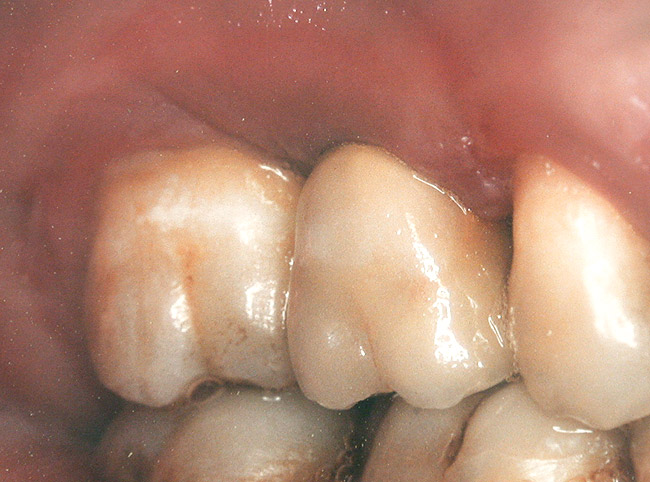

Case 3

A 53-year-old female was referred for evaluation of a fracture of tooth No. 24. The tooth had been treated endodontically 5 years prior. The radiograph revealed a complete fracture of the tooth involving the crown (Figure 12). Tooth extraction and immediate placement of a an implant that was 10 mm in length and 3.75 in diameter was planned.

At the time of surgery, the tooth was extracted without harvesting any mucosal flap because the implant site was prepared by means of a pilot drill bur (Figure 13) and alternating osteotomes (Figure 14A and Figure 14B). The implant was positioned and showed primary stability. The implant was loaded 2 days after surgery. Then, splinted PFM crowns supported by custom gold abutments were delivered. At 6 months posttreatment, the radiograph revealed no bone resorption and the clinical result was optimal (Figure 15A and Figure 15B).

Figure 14a  Alternating osteotomes were used to prepare the implant site.

Figure 14a

Figure 14b  Alternating osteotomes were used to prepare the implant site.

Figure 14b